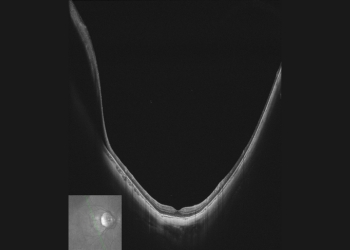

Anterior segment imaging with VG-200C

Imaging depth visualization of VG-200C